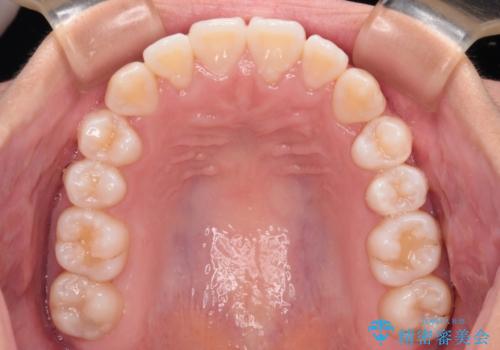

前歯のデコボコを楽して改善 ワイヤー装置による矯正治療

- 前歯のデコボコを治したいとのことで来院された患者様です。

インビザラインによるマウスピース矯正も適用となる歯列でしたが、できる限り楽して、短期間で治したいとのことで、ワイヤー装置にて矯正治療を行うこととしました。